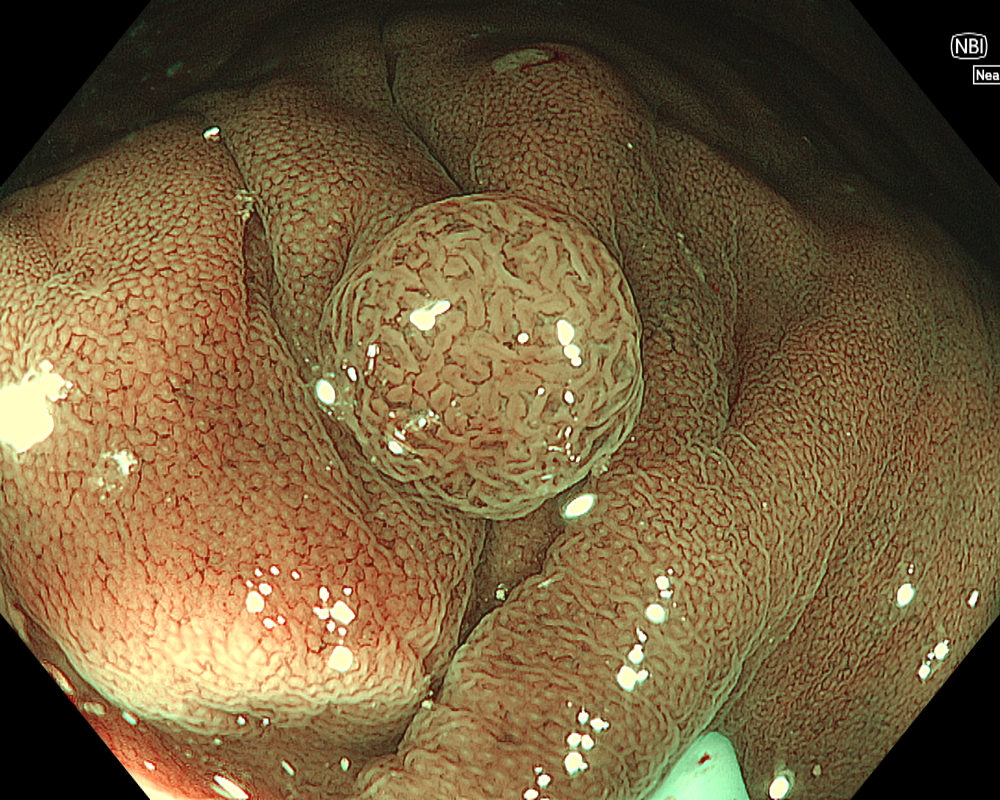

Figure 3: NBI image in near-focus mode under water immersion. Water immersion eliminates halation and provides clear images, while also enhancing magnification for more detailed observation.

Next, initiate observation by approaching the lesion. As mentioned, the CF-EZ1500D scope allows proximity up to approximately 3 mm even in normal mode. Switching to Near focus mode with a single button press allows for observation up to 1.5 mm. EDOF facilitates easy focusing on both near and far distances, making it possible to continuously capture images that are sharply in focus across the entire screen, even for lesions with uneven surfaces or those with motion due to respiratory variation. Observation under water is useful if halation is a concern or if more detailed observation is desired.

In addition to eliminating halation, underwater observation has a magnification effect. When combined with the Near focus mode, it allows for even clearer magnified images. For determining the indication for CSP, the JNET (Japan NBI Expert Team) classification is used, which evaluates the surface Vessel pattern and Surface pattern using NBI + Near focus magnified observation. If the lesion is classified as Type 2A (characterized by a regular caliber and regular distribution (meshed/spiral pattern) in the Vessel pattern, and a regular pattern (tubular/branched/papillary) in the Surface pattern), it is highly likely to be a lowgrade intramucosal neoplasia, and CSP can be indicated if the size is less than 10 mm. If the lesion is classified as Type 2B (characterized by variable caliber and irregular distribution in the Vessel pattern, and an irregular or obscure pattern in the Surface pattern), there is a higher possibility of high-grade intramucosal neoplasia or deeper invasion. Indiscriminately performing CSP based solely on small size should be avoided in these cases.